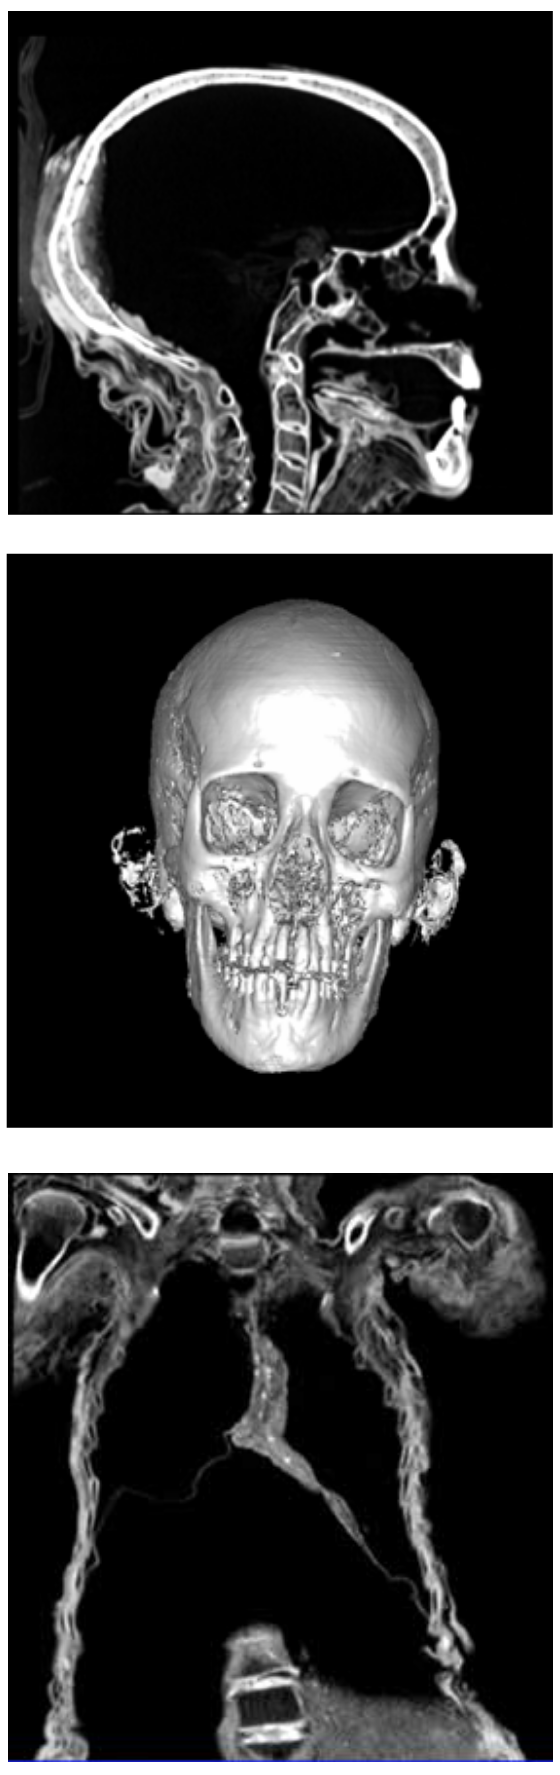

In the CT image to the left, the head is viewed from the side. The eye sockets are filled with linen packing and traces of packing can be seen in the nose and mouth. The “cloudy” material at the back of the skull is resin, which was poured into the skull through the nose after the brain had been removed.

The center image shows a reconstruction of her skull. The cartilage of her ears is also visible.